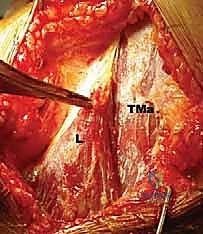

FIG 1 • A. Cadaveric dissection showing the interval between the teres major (TMa) and latissimus dorsi (L) tendons, with the radial nerve (R) deep to the latissimus and the axillary nerve (Ax) superior.

- Axillary Nerve: The axillary nerve runs superior to the latissimus dorsi tendon before exiting the quadrangular space. In neural rotation and adduction, the average distance between the nerve and the superior border of the tendon is 1.9 cm. Like the radial nerve, this distance increases with external rotation and abduction and decreases with internal rotation.

FIG 1 • C. Cadaveric dissection of the superficial muscular anatomy of the posterior shoulder, showing the axillary nerve (Ax) exiting the quadrilateral space.

- Anterior Humeral Circumflex Artery: This vessel runs along the superior border of the latissimus dorsi tendon.

- Surgeon's Directive: "Maintain constant awareness of the radial nerve. It lies anterior to the latissimus. We'll internally rotate and adduct the arm to increase its distance from our working field, but we must protect it throughout this release."

> PITFALL: Radial Nerve Injury. The radial nerve is extremely vulnerable during the release of the latissimus dorsi tendon from the humerus. Keep the arm in abduction and external rotation as much as possible during this phase to maximize the distance between the nerve and the tendon's superior border. Use a blunt instrument (e.g., a small Hohmann retractor) to gently sweep and protect the nerve before cutting the tendon.

FIG 4 • B. The latissimus dorsi (L) is identified and separated from the teres major (TMa).